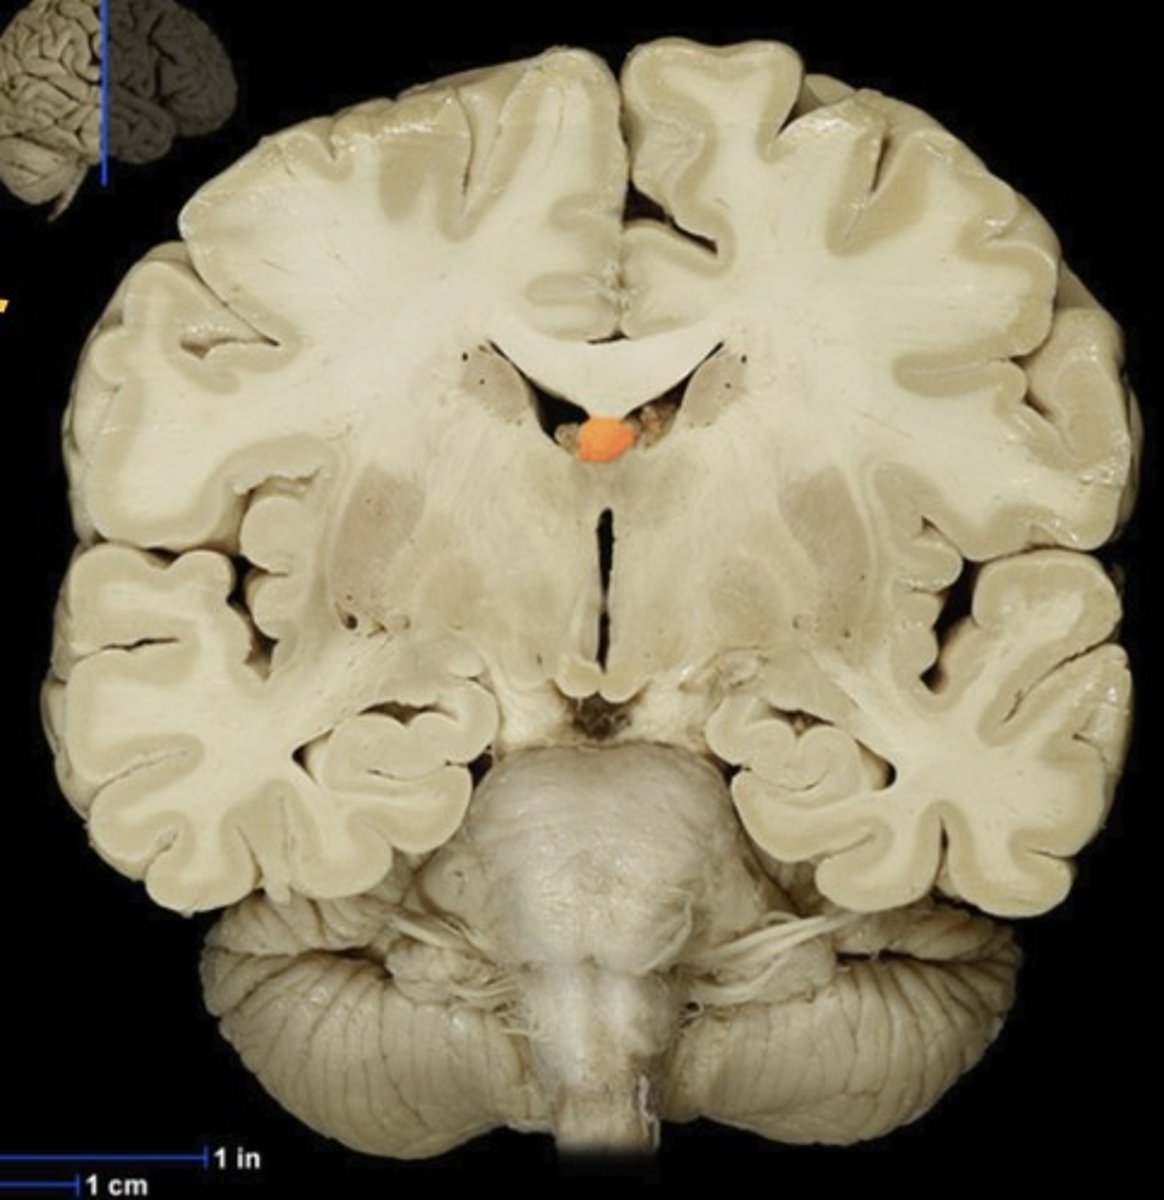

Name this structure

Putamen